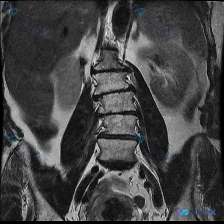

整理到一个有点意思的影像读片案例,大家可以先聊聊第一眼思路。 --- 基本情况 - 输入指向:“脊柱侧弯” - 提供的影像:腰椎MRI T2序列-冠状位 影像科客观描述(摘要): 1. 脊柱排列:腰椎序列基本连续,未见明显的侧弯畸形或明显的椎体滑脱;双侧髂嵴高度大致对称。 2. 椎间盘:L4/L5及...